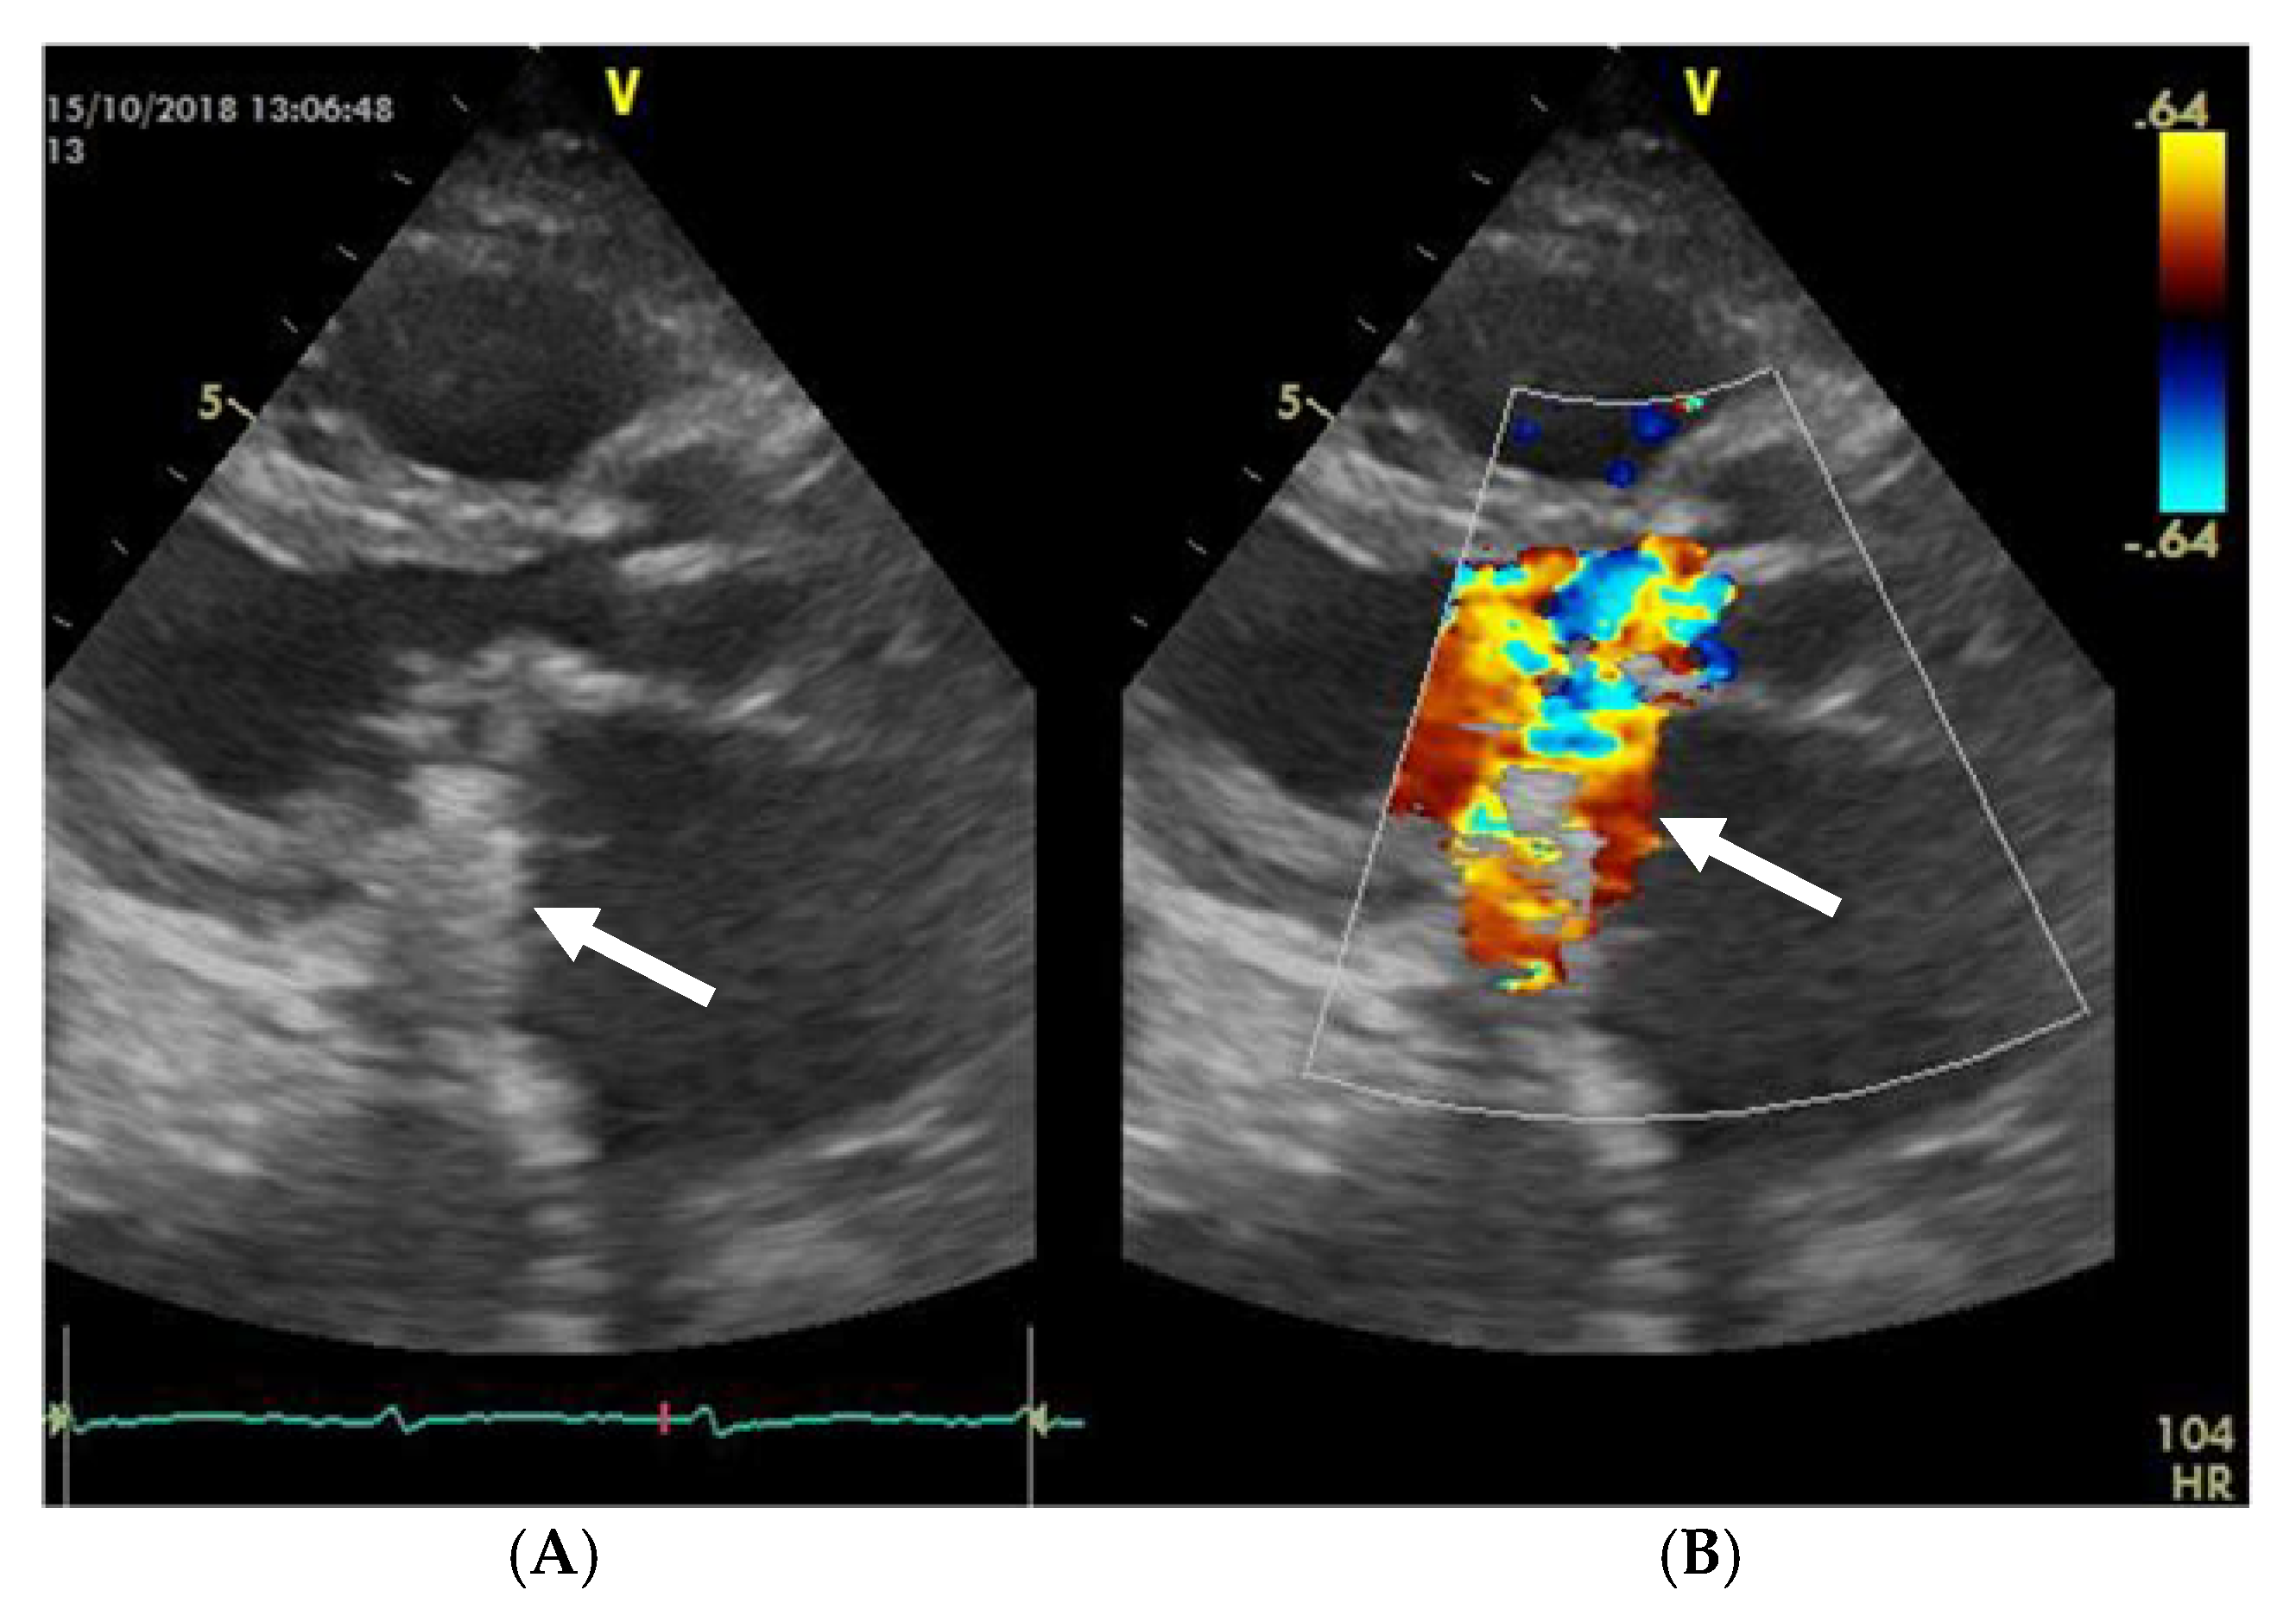

The mobility of the discs and the presence of pathological features such as thrombus, pannus, or vegetation are evaluated using bidimensional echocardiography. The thrombus can sometimes be difficult to visualize; in some cases, it appears as an echodense mass that is located on the discs and restricts their motion (Figure 2A) [17]. The colour Doppler flow quantification may reveal a turbulent flow above the valve or even the absence of colour flow through the prosthesis (Figure 2B). While 2D imaging leaves room for ambiguity in terms of thrombus localization in relation to the prosthesis, 3D images clearly reveal the relationship between them, as illustrated in the moving images of Video S1 (Supplementary Material). The evaluation of intracardiac masses suspected for thrombi using pulsed wave (PW) tissue Doppler imaging (TDI) might be an improvement over visual assessment, as it provides a more precise definition of mass mobility [18,19].

Figure 2.

(A) TTE. Prosthetic mitral valve PLAX thrombus on the disc left atrial side (arrow). (B) TTE. Colour Doppler turbulent flow above the prosthesis (arrow).